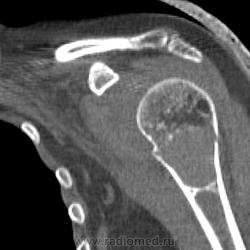

или гигантоклеточная опухоль. Требуется морфологическая верификация

Интересно, что структура разная, кость не вздута, кортикал истончен, но сохранен. Болей до травмы совершенно не было. Думаю, травматологи прооперируют, надеюсь узнать результаты гистологии - сообщу. Спасибо. Татьяна Валентиновна. Я сначала на аневризмальную кисту подумала, но не уверена была.

При ГКО бывает вторичная аневризмальная киста